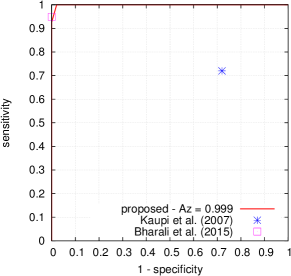

FROC curves are reported in Fig. 6 for ‘net B’; areas under the limited FROC curve for all three ConvNets are summarized in Table 3. It appears that the number of false alarms is rather large, particularly in the case of microaneurysm detection. The reason is that human experts primarily segmented the most obvious lesions, while screening algorithms need to focus on the most subtle lesions as well. In other words, many true lesions are counted as false alarms. Of course, this comment also applies to competing automatic solutions. To show the value of our detections, the proposed solution was compared in Fig. 7 to results reported in the literature, following the DiaretDB1 standardized procedure (see section 5.3.2). Most authors reported a single (sensitivity, specificity) pair: this is what we reported in Fig. 7. Some authors reported ROC curves; in that case, we also reported a single (sensitivity, specificity) pair: the one closest to the (sensitivity = 1, specificity = 1) coordinate. Note that all competing solutions (Kauppi et al., 2007; Yang et al., 2013; Franklin and Rajan, 2014; Kumar et al., 2014; Bharali et al., 2015; Mane et al., 2015; Dai et al., 2016) are trained at the lesion level, while ours is trained (in Kaggle-train) at the image level.

Three ConvNets were trained to detect referable DR in the Kaggle-train dataset, using the proposed heatmap optimization procedure. Then, we evaluated how well those ConvNets could detect lesions in the DiaretDB1 dataset, without retraining them. For lesion detection at the image level, they outperformed previous algorithms, which were explicitly trained to detect the target lesions, with pixel-level supervision (see Fig. 7). This superiority was observed for all lesions or groups of lesions, with the exception of ‘red lesions’. Experiments were also performed at the lesion level: for all lesion types, the proposed algorithm was found to outperform recent heatmap generation algorithms (see Table 3). As illustrated in two examples (see Fig. 9 and 10), the produced heatmaps are of very good quality. In particular, the false alarms detected on the vessels, in the vicinity of true lesions in the unoptimized heatmaps ( maps), are strongly reduced with sparsity maximization (, , ). These experiments validate the relevance of image-level supervision for lesion detectors, but stress the need to optimize the heatmaps, as proposed in this paper. Note that detection performance is not affected much by image quality: very good detections are produced in the blurry image obtained with a low-cost, handheld retinograph (see Fig. 10). This is a very important feature, which opens the way to automated mobile screening. However, it can be observed that the ‘AlexNet’ architecture, which achieves moderate DR detection results, also achieves poor detection results at the lesion level, even after heatmap optimization (see Table 3): to ensure good detection performance at the lesion level, the proposed optimization framework should be applied to ConvNet architectures that achieve good image-level performance.